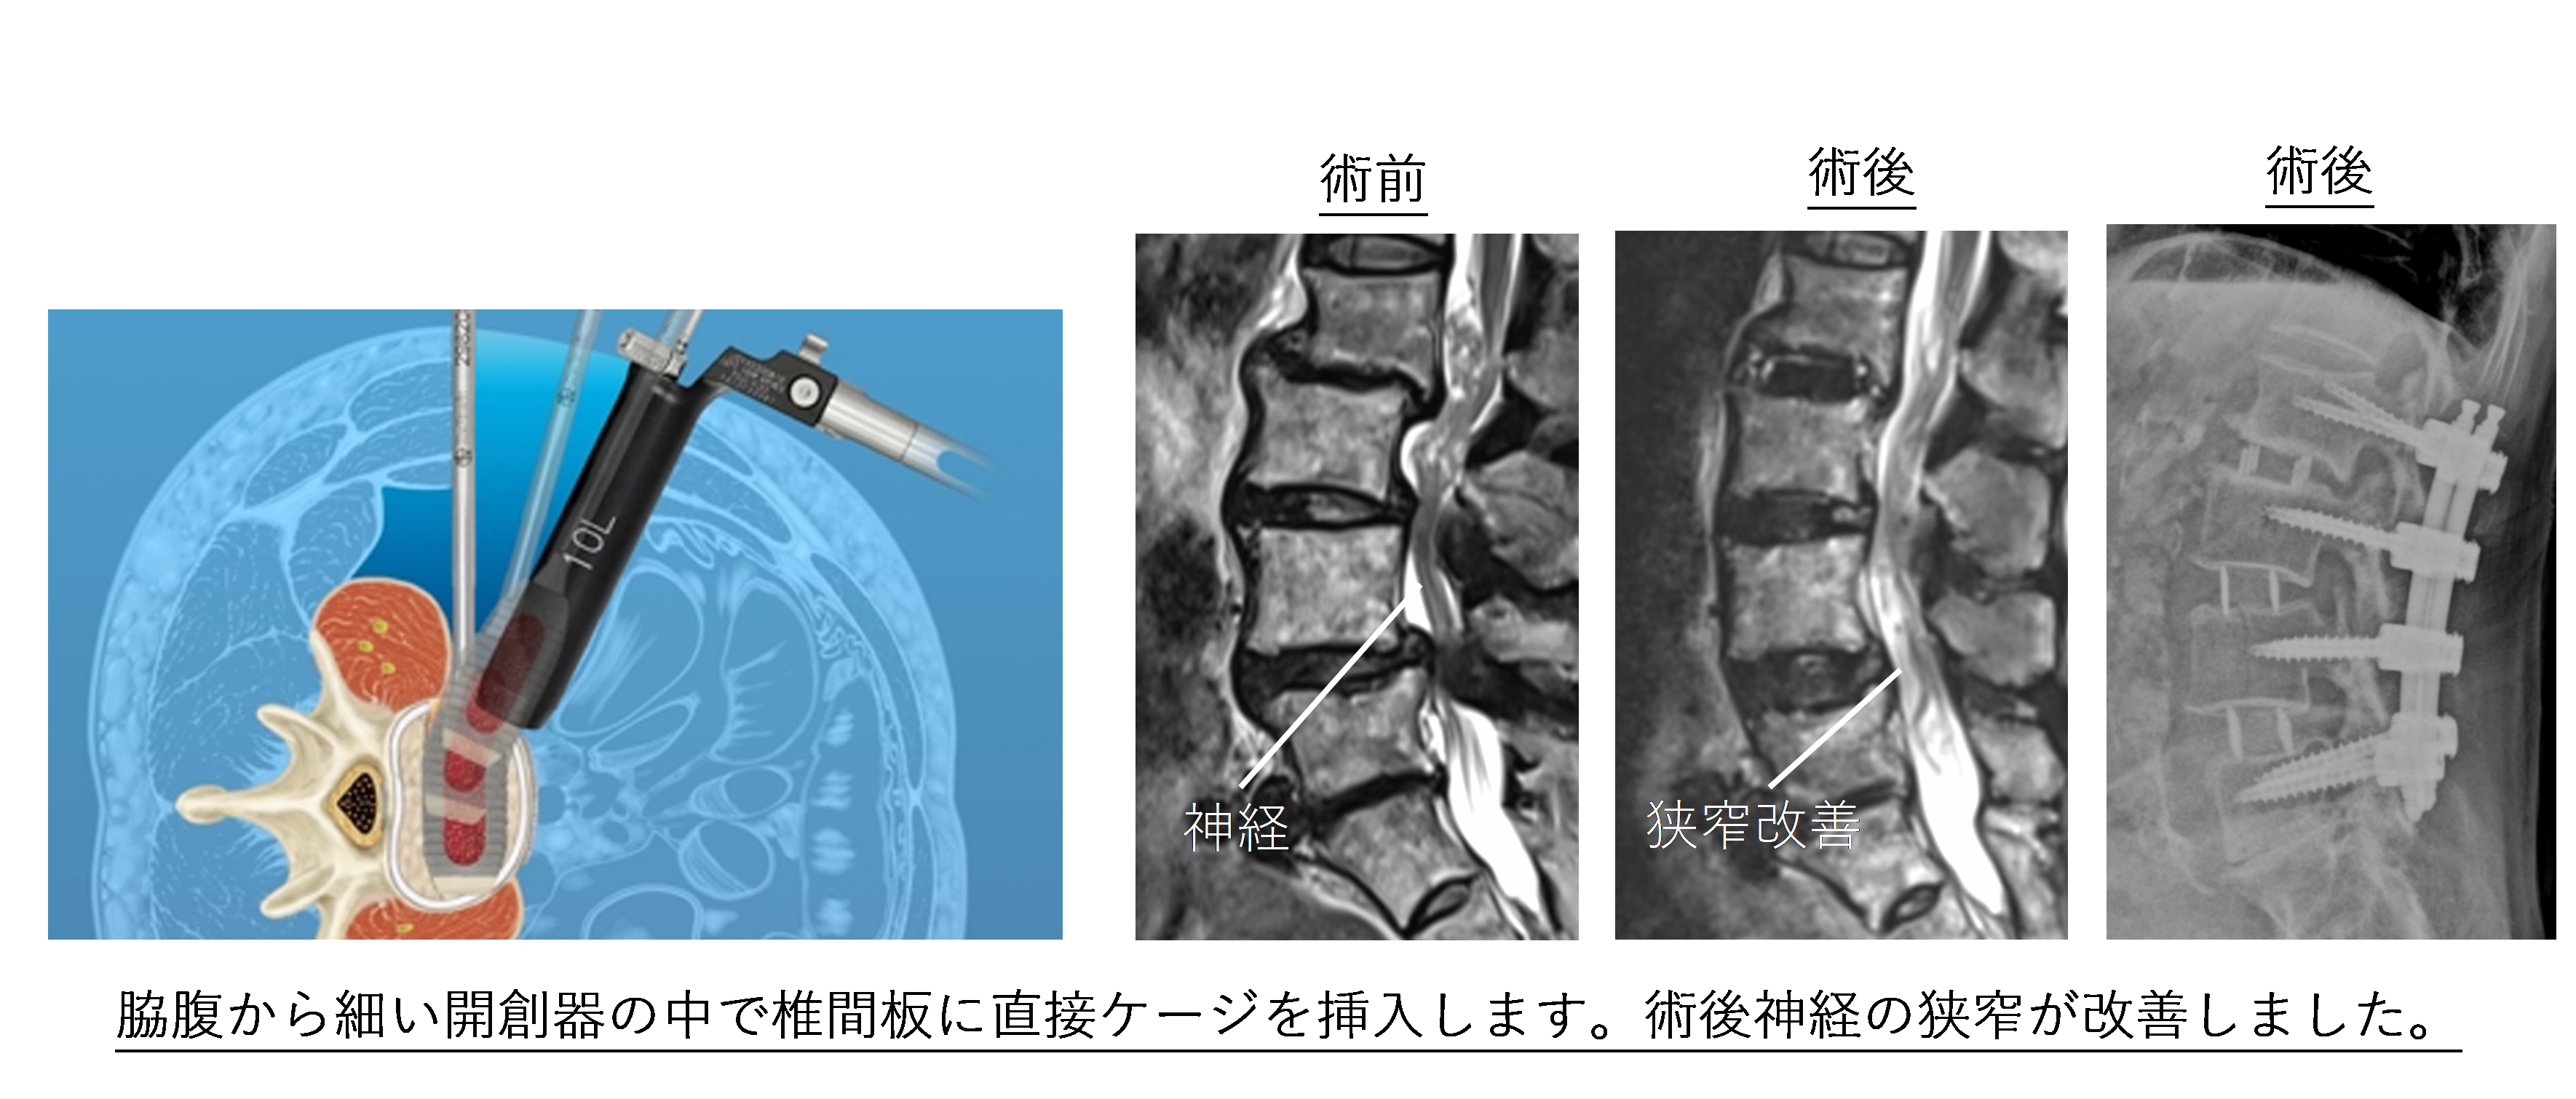

側方進入腰椎椎体間固定術 (eXtreme Lateral Lumbar Interbody Fusion:XLIF, Oblique Lateral Lumbar Interbody Fusion: OLIF)

適応:腰部脊柱管狭窄症, 腰椎変性すべり症、変性側弯症、腰椎分離症など

この術式は椎間板を取り除き、ケージを設置する術式です。以前は大きな皮膚切開を必要とした術式ですが、開創器や光源の進化によりわずか数センチの傷で手術可能となりました。日本に2013年に導入され、認定された施設のみで施行可能な術式です。本術式は大きなケージを挿入することができるため、曲がった背骨をより矯正しやすいなどのメリットがあります。また側腹部より椎間板にアプローチするため背筋を損傷することがなく、体への負担が少ないのが特徴です。可能な病態にはこちらの術式を選択します。術後2日より歩行を開始し、2,3週間で歩行が安定し退院可能となります。